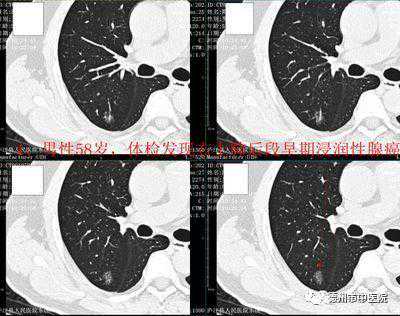

2、每天下午进行低剂量肺结节CT筛查(优惠后200元),适用于早期肺癌的筛查,在降低辐射剂量的前提下,为您的健康保驾护航。

什么是低剂量螺旋CT?低剂量螺旋CT是用最小的扫描范围,最低剂量,最少的X线量,对病变作出诊断。因为螺旋CT,常规一次扫描辐射量大概是3-5mSv,低剂量大概是1mSv,辐射量可以缩小2/3,对病变的检查也可以作出的准确的诊断。相比传统的常规CT检查,一个是剂量小,使病人受到辐射小,对微小结节也能够清楚地显示。常规用于体检或者肺部微小结节的追踪观察,这样使病人能够得到准确的诊断,然后又不接受更多剂量的X线。